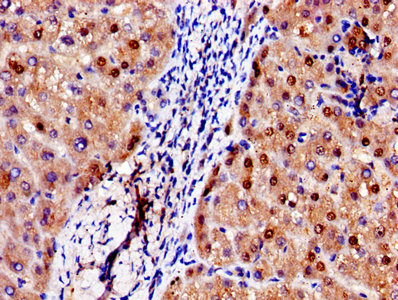

Immunohistochemistry of paraffin-embedded human liver tissue using CSB-PA001311LA01HU at dilution of 1:100